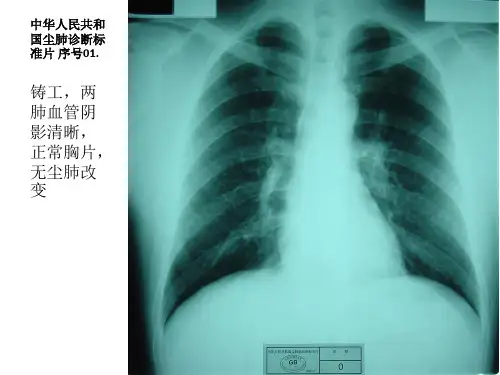

4.1 无尘肺(0)[1]

a)0:X射线胸片无尘肺表现。

b)0 :胸片表现尚不够诊断为I者。

(一)无尘肺(代号O)

1. O:X线胸片无尘肺表现。

2. O+:胸片表现尚不够诊断为“Ⅰ”者。